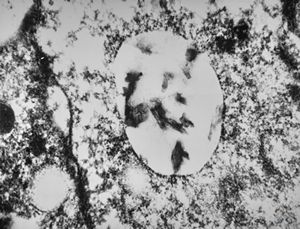

F,3y. | toxoplasmosis